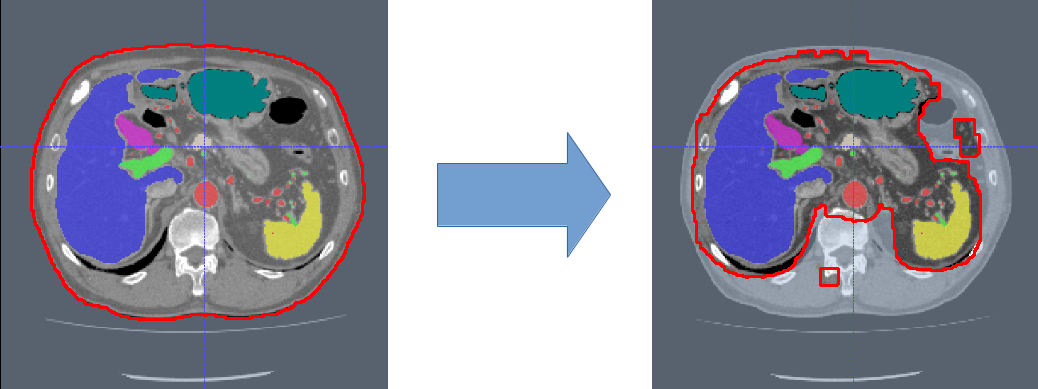

To overcome this limitation, we learn a second-stage FCN that is fine-tuned from a first-stage FCN in a hierarchical manner and hence focuses more on the boundary regions. This is a coarse-to-fine approach in which the first-stage FCN sees around 40% of the voxels using only a simple mask of the body created by thresholding the image. In the second stage, the amount of the image’s voxels is reduced by around 10%. In effect, this step narrows down and simplifies the search space for the FCN to decide which voxels belong to the background or any of the foreground classes; this strategy has been successful in many computer vision problems. Our approach is illustrated on a training example in Fig. 1. In contrast to previous approaches of multi-organ segmentation where separate models have to be created for each organ Oda et al. (2016), Tong et al. (2015), our proposed method allows us to use the same model to segment such very different anatomical structures as large abdominal organs (liver, spleen), but also vessels like arteries and portal veins. In contrast, other recent FCN-based methods are applied to medical imaging were often constrained to using rectangular bounding boxes around single organs and performing slice-wise processing in 2D Roth et al. (2017), Zhou et al. (2016), Christ et al. (2016).

In the first stage, we apply simple thresholding in combination with morphological operations (hole filling and largest component selection) to get a mask of the patient’s body in a slice-by-slice fashion. This mask can be utilized as candidate region to reduce the number of voxels necessary to compute the network’s loss function and reduce the amount of input 3D regions shown to the CNN during training to about 40%. After training, the first-stage FCN is applied to each image to generate candidate regions for training the second-stage FCN (Fig. 3). We define the organ labels in the testing phase using the of the class probability maps. Any foreground label is then dilated in 3D using a voxel radius of . We compare the recall and false-positive rates of this first-stage FCN with respect to for both the training and validation sets in Fig. 2. gives good trade-off between high recall (99%) and low false-positive rates for each organ on our training and validation sets.